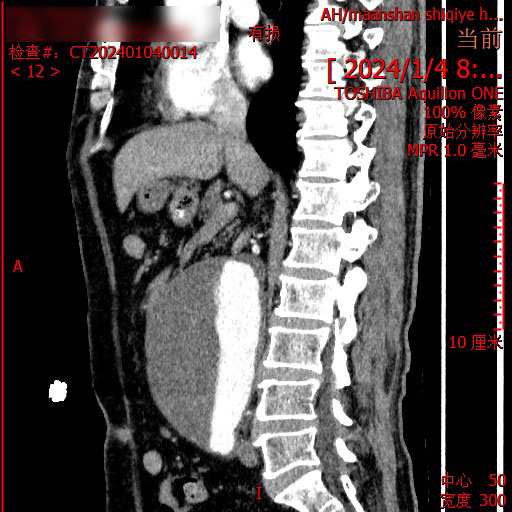

正当一家人走投无路之际,在朋友的介绍下,2024年1月,患者来到了马鞍山十七冶医院肿瘤精准诊疗中心,刘永彪主任携团队亲自为他量身定制了治疗方案,考虑到腹主动脉夹层,同时召集医院感染科、老年病科、心血管内科、肿瘤科等专家进行会诊。经过一系列的检查,明确病情,直肠中分化腺癌,虽然有手术指征,但伴有腹主动脉巨大瘤,手术风险极高,综合考虑建议先进行放射治疗,患者家属听到可以治疗如释重负,喜极而泣。

2024年1月,患者开始精准定位,进入肿瘤内科进行放射治疗,过程中,主任和他的团队每日至少查房两次,以便观察患者的病情变化,及时调整放疗计量,减少并发症给患者带来的痛苦。因为腹主动脉瘤的高危性,整个治疗过程中,医护人员操作轻柔,治疗仔细,减少副反应给患者腹部带来的刺激。没想到经过第一阶段的放射治疗后,患者的病情便得到有效缓解,便秘、腹泻等症状逐渐减轻。“简直就是奇迹!真没想到放射治疗效果就那么好,这让压在我们心口的石头终于落了地,十七冶医院肿瘤精准诊疗中心的专家医术高明,医德高尚,是咱马鞍山老百姓的福气。”患者家属夸赞道。